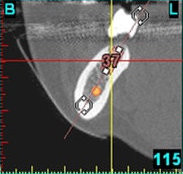

(siehe Bild 3 und 4).

Mit diesen gewonnenen Informationen und Planungen stellt der Zahnarzt interaktiv spezielle Bohrschablonen her. Diese ermöglichen eine exakte Positionierung der Implantate, so wie vorher am Computer geplant.

Weiterhin ist eine auf diese Weise geplante Operation für den Patienten weit weniger belastend. Denn die Freilegung des Knochens ist auf ein Minimum reduziert.